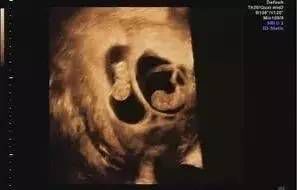

其实不然,四维超声检查只是系统超声中的一个检查项目,可以展示面部的漂亮图像加强父母与胎儿的情感纽带。在对孩子的外部结构异常、中枢神经系统、骨骼系统等等检查中,四维超声能够为我们提供更加直观的诊断信息。